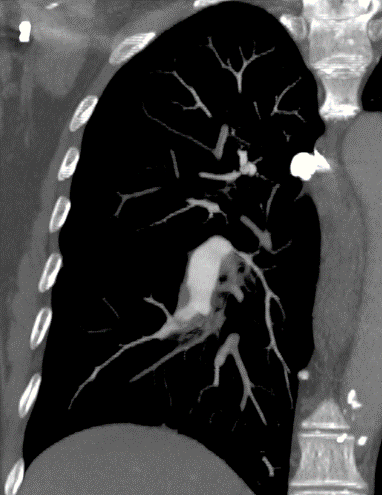

Airway disease - Bronchiectasis

Irreversible localized or diffuse bronchial dilatation, usually resulting from chronic infection, proximal airway obstruction, or congenital bronchial abnormality.